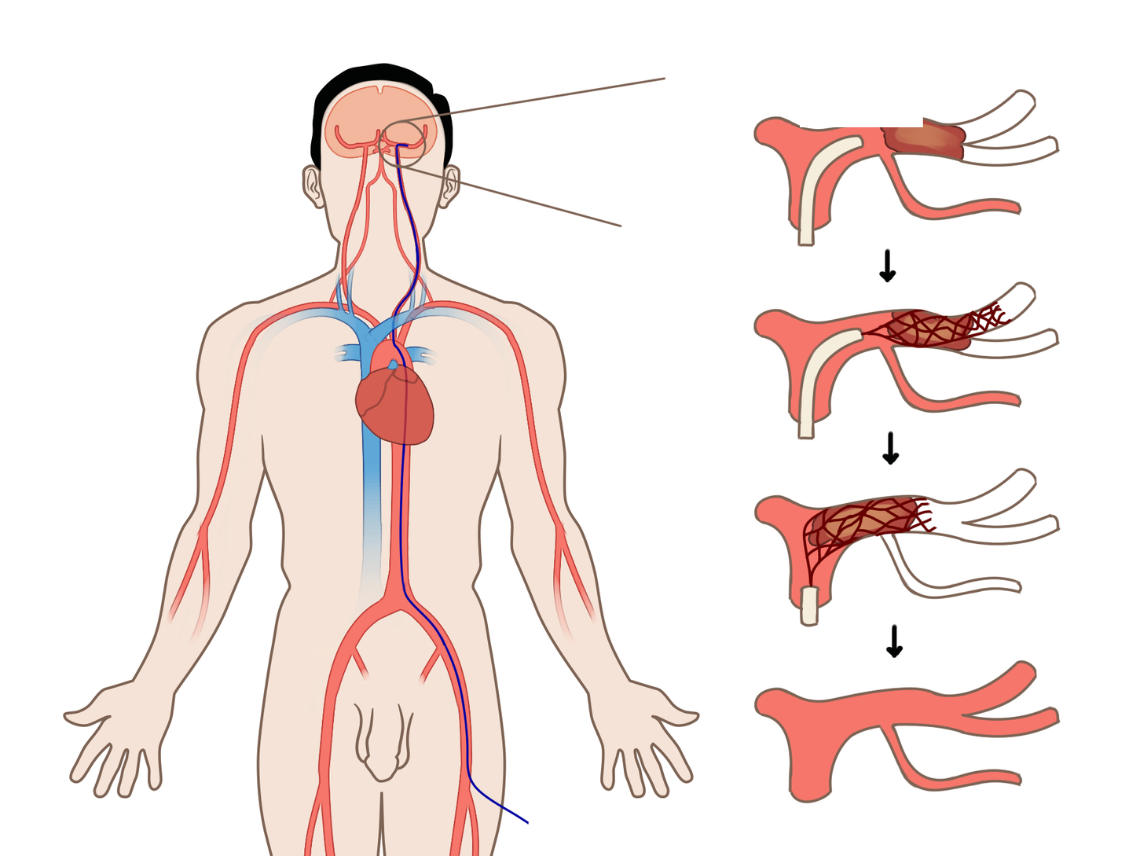

A range of Invasive diagnostic procedures and treatments performed at the radiology department

Frequently performed image guided procedures